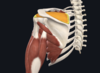

- deltoid

- lateral third of clavicle; acromion and spine of scapula; deltoid tuberosity of humerus

- axillary nerve

- anterior fibres- flexion and medial rotation; posterior fibres- extension and lateral rotation; middle fibres- major abductor of the arm (beyond 15degrees)